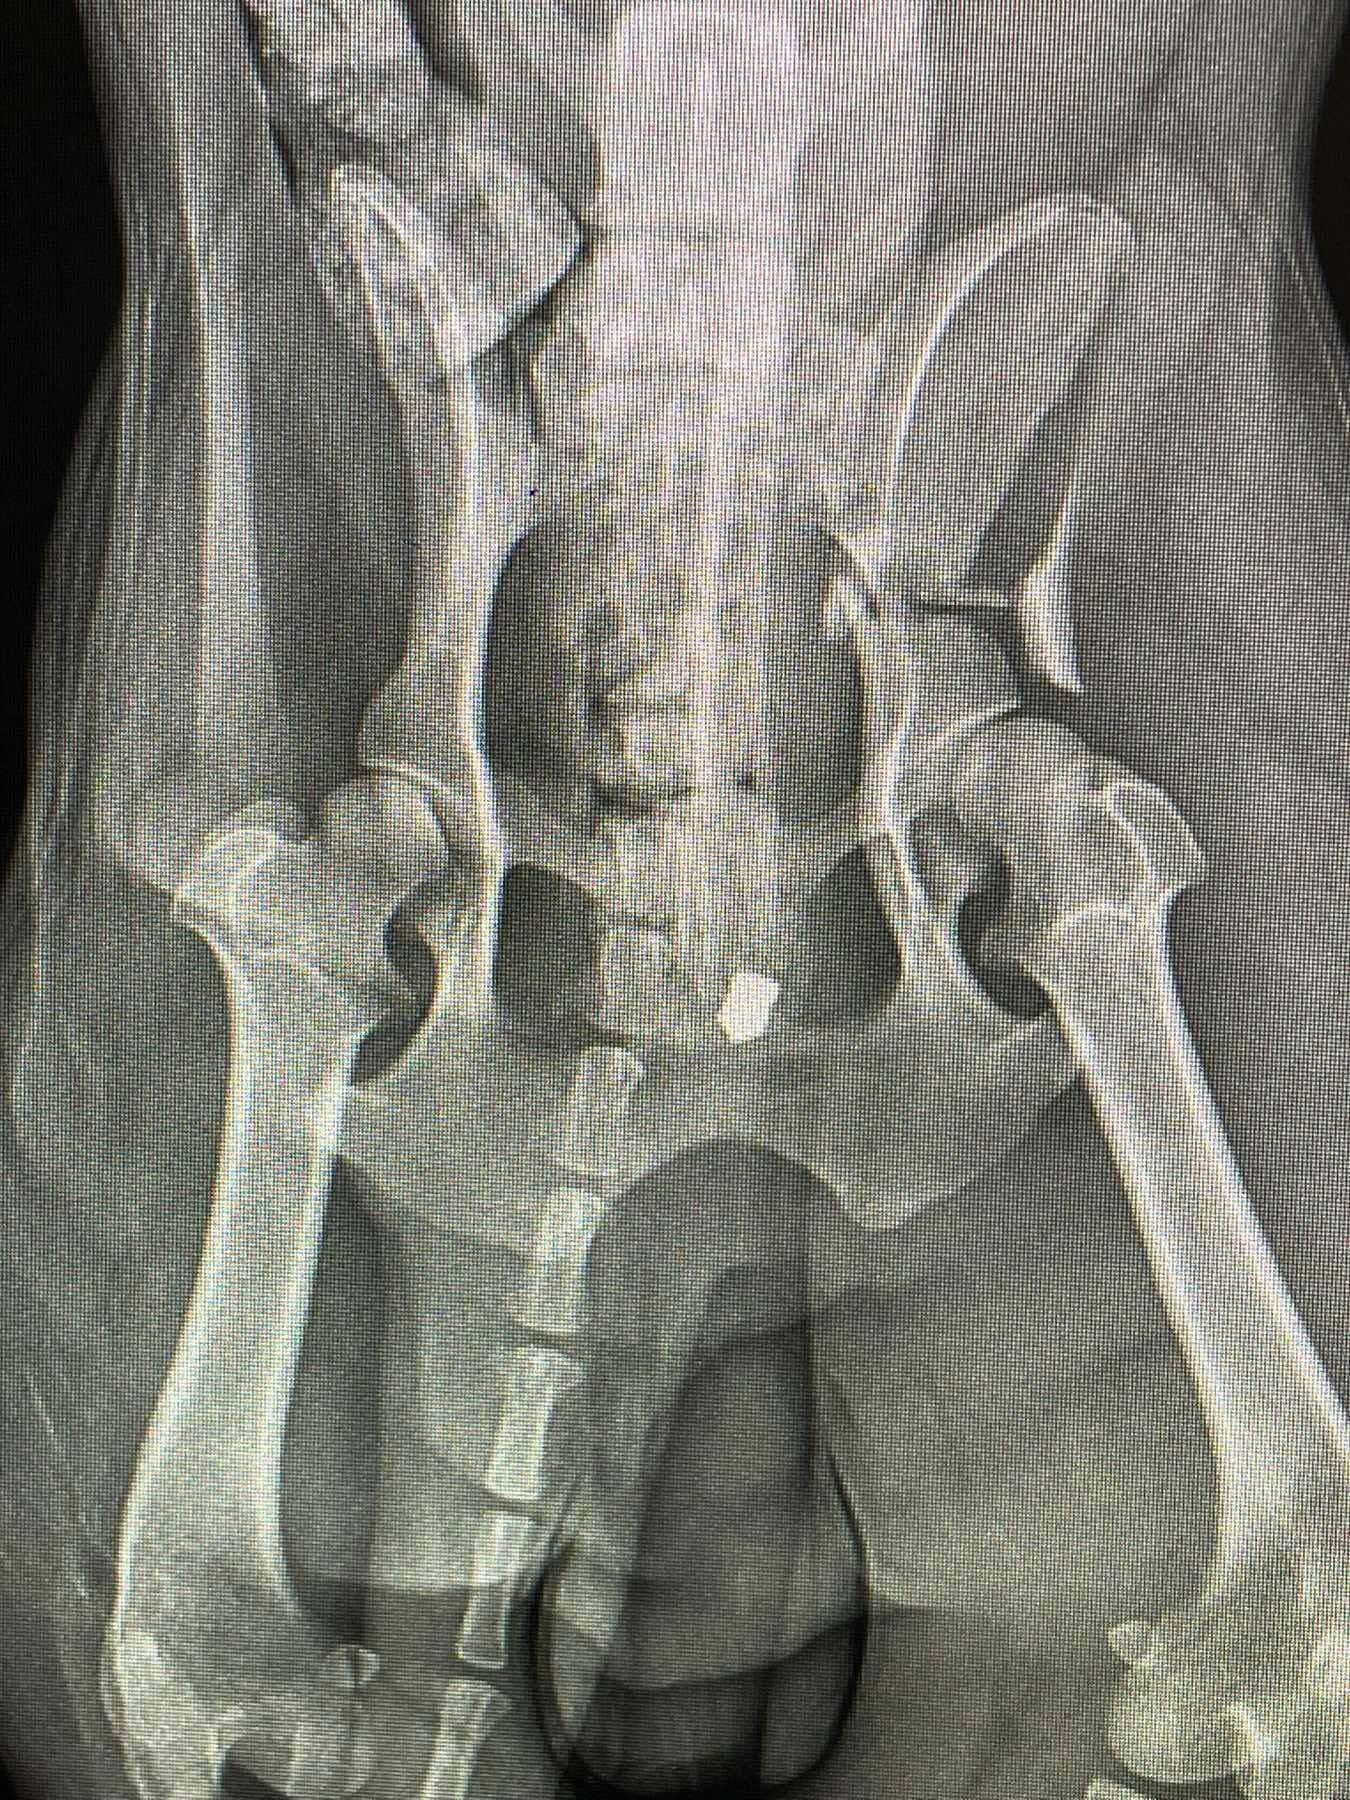

Як зазначено в дописі, огляд та рентген показали наявність у тілі тварини двох куль. Окрім цього, у собаки роздроблені кістки на лапі.